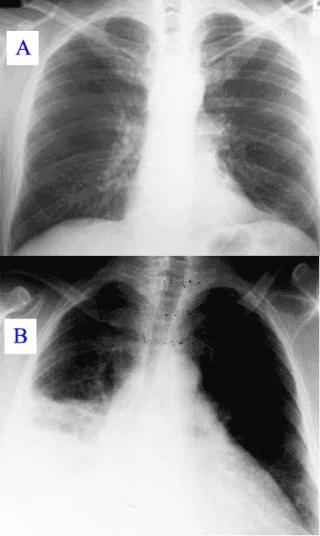

Pendant sa progression, la maladie peut évoluer vers une pneumonie atypique, qui peut mettre en cause le pronostic vital en raison d’un syndrome de détresse respiratoire aiguë (source : Wikipedia)